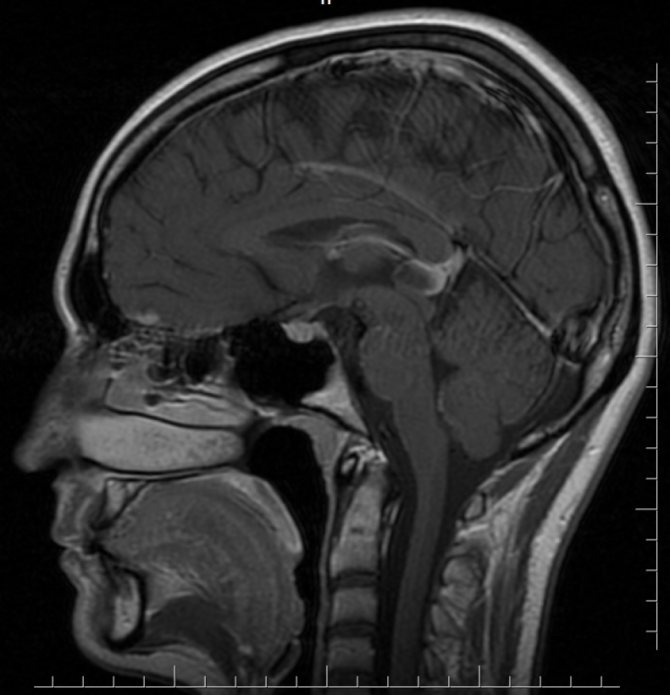

Заболевание является крайне редким и всегда носит доброкачественный характер. Обнаружение кисты шишковидной железы происходит случайно при проведении МРТ либо других обследований мозга. Патология долгое время не проявляет себя, и человек может не подозревать о ее существовании.

Если киста шишковидной железы не вызвана паразитарной инфекцией, то она никак не дает о себе знать и ее обнаруживают случайно при диагностики других патологий. В других случаях, при наличии ярко выраженной симптоматики, врач может назначить следующие обследования:

- МРТ и рентген помогают увидеть заполненное секретом образование в головном мозге.